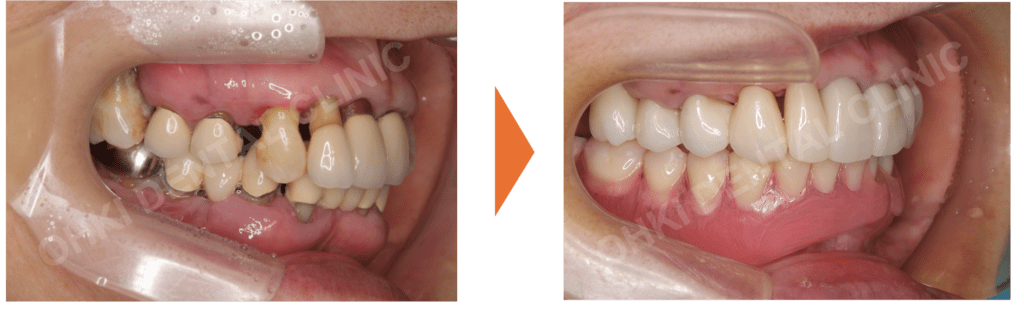

「歯ぐきが下がって、見た目が悪くなってきた」「前歯が伸びてきて唇に当たる」……。そんな切実なお悩みで来院された68歳女性の症例です。

重度の歯周病によりお口全体が崩壊しつつある状態でしたが、約1年間の精密な計画治療により、再び自信を持って笑える理想の口元を取り戻されました。

・重度の歯周病(Pタイプ)により、すでに多くの歯を失っている状態でした。

・不適合な補綴物(被せ物)が多数あり、残っている歯も歯周病で保存が難しいものが含まれていました。

・全体的に欠損が大きく、機能的な崩壊が見られる状態でした。

仕上がりの特徴

- スマイルラインが非常に綺麗に改善され、若々しい口元になりました。

- 前歯から奥歯までしっかり噛めるようになり、機能的な回復を遂げました。

- 初診時と比べ、咬合平面(噛み合わせのライン)が整い、痛みや違和感なく食事ができるようになりました。